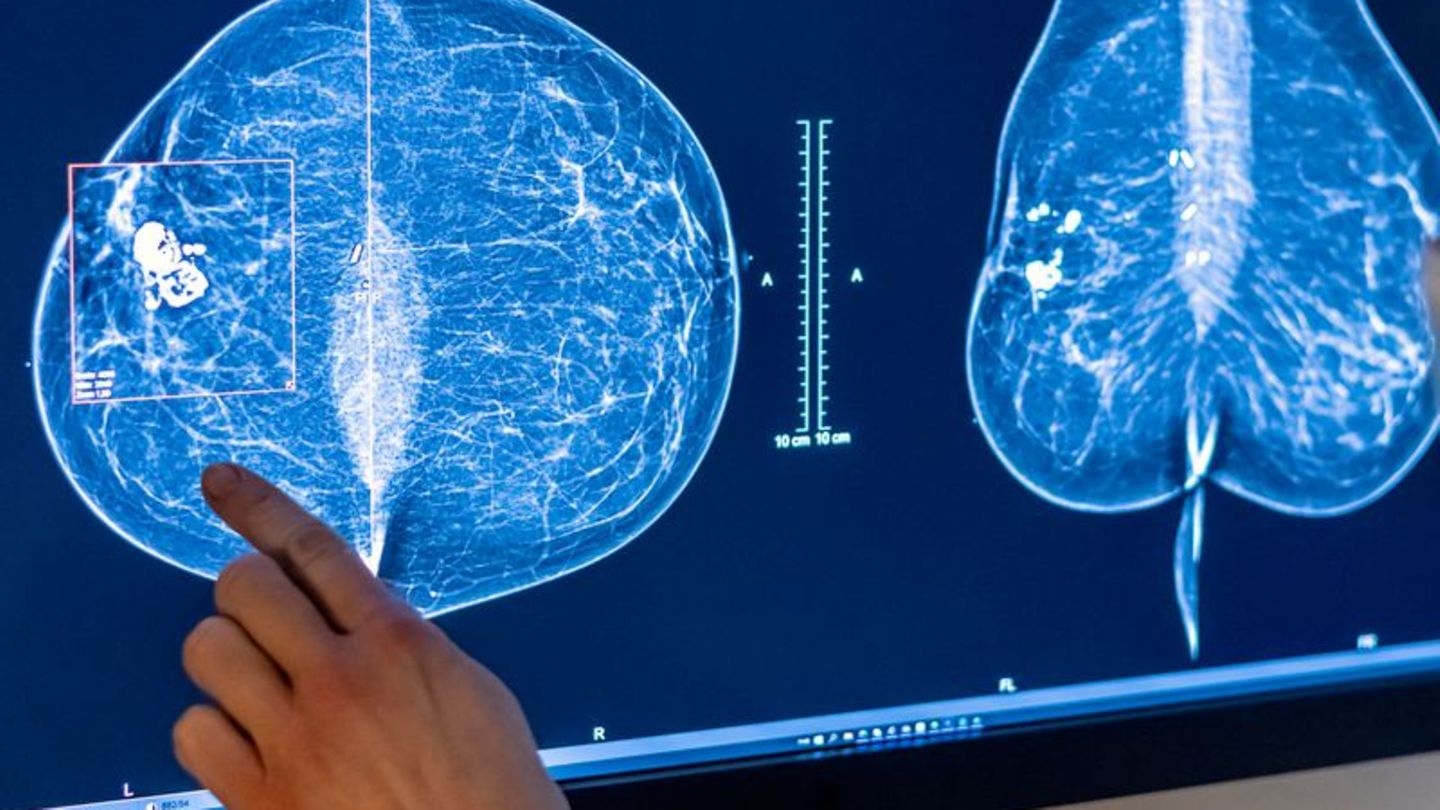

2023 wurden rund eine halbe Million Menschen in Deutschland mit Krebs diagnostiziert. (Symbolbild) Foto: Hannibal Hanschke/dpa

2023 wurden rund eine halbe Million Menschen in Deutschland mit Krebs diagnostiziert. (Symbolbild) Foto

© Hannibal Hanschke/dpa